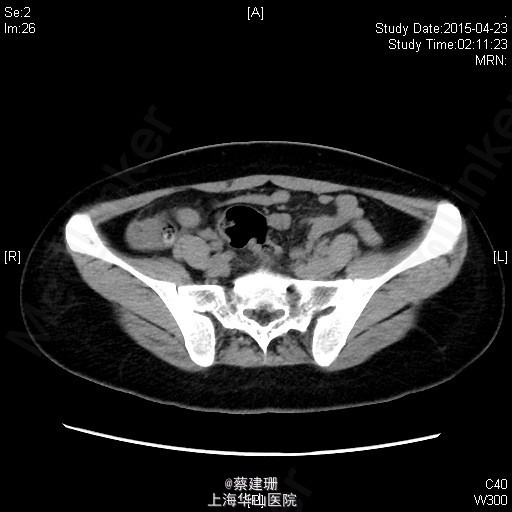

急性阑尾炎(粪石?)伴局限性腹膜炎

患者 女性 24岁,因“转移性右下腹痛一天余。”入院。患者一天前无明显诱因下出现中上腹疼痛,无恶心呕吐,无腹泻。10小时前疼痛转移至右下腹,原先中上腹疼痛缓解,无发热无腹泻。患者未予重视,后疼痛难忍于今日凌晨至我院急诊就诊,血常规示:WBC:18.63*10^9/L,我院B超示:右下腹见肠段局限性扩张,炎性病灶待排。肝胆胰脾肾未见明显异常,双输尿管未见扩张。我院CT示:阑尾增大壁增厚内见高密度影及低密度气体影,符合阑尾炎改变,盆腔少量积液。患者拒绝行急诊手术,故予以保守治疗,患者症状未缓解,右下腹疼痛加重。为行进一步诊治,收入院。

全身皮肤粘膜未见异常,无肝掌,全身浅表淋巴结无肿大。腹平坦,腹壁软,右下腹压痛,伴有肌紧张及反跳痛,麦氏点压痛(+),肝脾肋下未触及,肝肾脏无叩击痛,肠鸣音4次/分。 辅助检查:血常规示:WBC:18.63*10^9/L,N:89%。我院B超示:右下腹见肠段局限性扩张,炎性病灶待排。肝胆胰脾肾未见明显异常,双输尿管未见扩张。我院CT示:阑尾增大壁增厚内见高密度影及低密度气体影,符合阑尾炎改变,盆腔少量积液。

入院后诊断:急性阑尾炎伴局限性腹膜炎。完善相关检查,全麻下行腹腔镜下阑尾切除术。术后恢复可,伤口无明显渗出,予以出院。